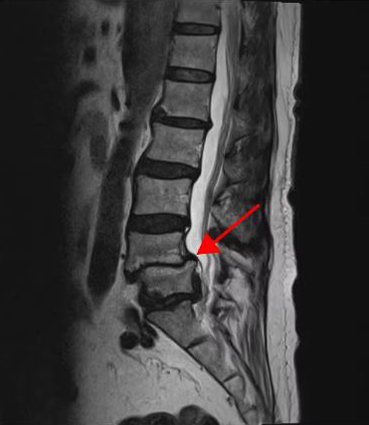

<4-5번 척추전방전위증>

<5-1번 디스크 파열>

이 환자분의 허리 MRI를 보면 4번, 5번 오른쪽에 심한 추간공협착증과 2단계의 척추전방전위증이 있는데, 특히 척추전방전위증 때문에 추간공이 많이 좁아져 있는 상태입니다. 또 왼쪽의 다른 마디에 디스크 파열이 있으나 환자분이 왼쪽으로는 증상이 전혀 없는 것으로 보아 이 디스크 파열은 통증을 일으키지 않는 무증상의 디스크 파열입니다.

이렇듯 4번, 5번 마디의 심한 추간공협착증과 척추전방전위증으로 인해 이 환자분은 다리에 마비가 왔고, 발목에 힘이 빠져 거의 걷지 못하는 상태였습니다. 새벽에 잠에서 깨 화장실을 갈 때는 네 발로 기어갈 정도로 증상이 심했습니다. 신경주사도 많이 맞아봤지만 통증이 전혀 줄지 않아서 결국 수술을 결심하셨는데요. 대학병원을 비롯해 정형외과 및 신경외과 등 아홉 군데 병원에서 진료를 받았지만, 어려운 수술이라고 말하면서 척추유합술, 감압술 등 병원마다 제시하는 수술방법이 다 달라 큰 혼란을 겪으셨습니다. 게다가 수술 후 후유증이나 잔존 증상에 대한 물음에 ‘있을 수도 있고 없을 수도 있다’라는 의사의 말에 수술을 고민하던 중 마지막이라는 생각으로 저희 모커리에 내원하셨습니다.